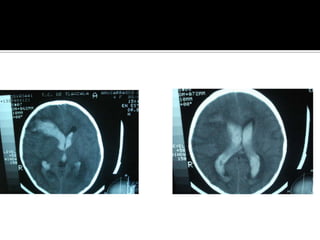

Signos tempranos:  TAC en EVC AgudoSigno dela arteria cerebral media hiperdensaAtenuacion del nucleo lenticularHipodensidad cortical o subcorticalEdema cerebralBorrado de la region insularBorrado de surcos corticalesCompresion ventricularAtenuacion de contraste cortico-medular